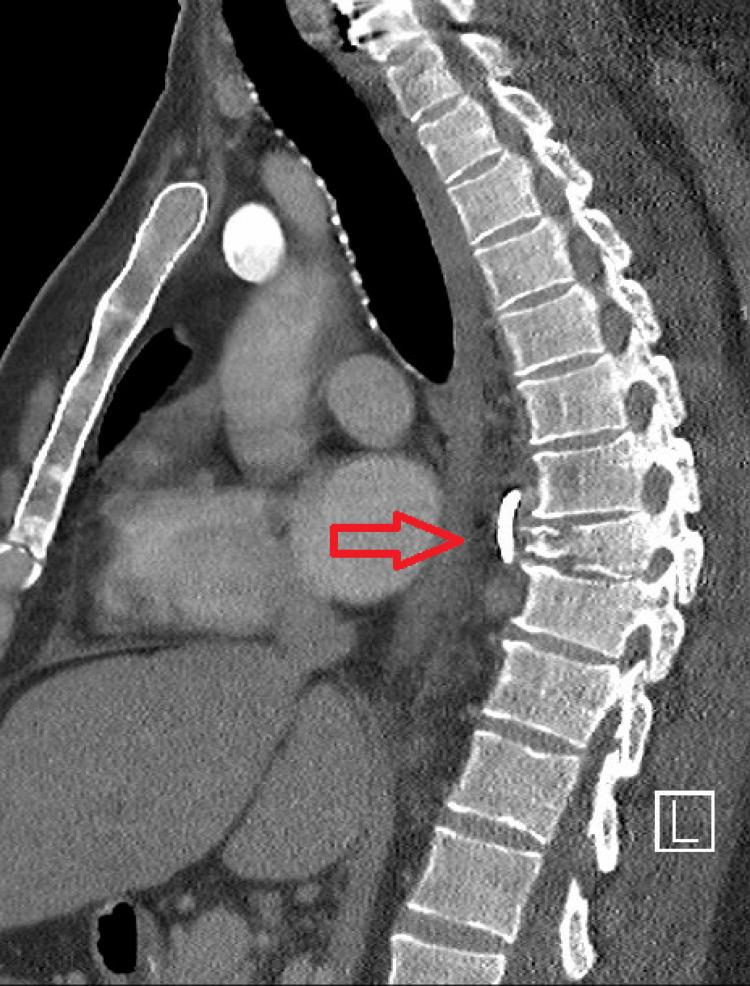

Vertebral (spinal) osteomyelitis is a rare spinal infection of the vertebral column that can be caused by bacteria or fungi. Though the initial treatment for all patients with vertebral osteomyelitis consists of antibiotics, surgery can be indicated in certain cases, such as in the presence of spinal instability or when antibiotics are not successfully eliminating the infection. Achieving spinal stability can be an important component of treating fracture-related infections, as instability can cause local damage and disrupt the healing process. The authors present the case of a patient with vertebral osteomyelitis that was not resolving with the administration of antibiotics in the context of a spinal fracture. A minimally invasive surgery was performed to achieve spinal stability and the infection soon resolved with antibiotics.

脊椎骨髓炎是一种罕见的脊柱感染疾病,可由细菌或真菌引起。虽然所有脊椎骨髓炎患者的初始治疗都包括使用抗生素,但在某些情况下,如存在脊柱不稳定或抗生素未能成功消除感染时,可能需要进行手术。实现脊柱稳定是治疗骨折相关感染的重要组成部分,因为不稳定会导致局部损伤并干扰愈合过程。作者介绍了一例脊椎骨髓炎患者的病例,该患者在脊柱骨折的情况下使用抗生素治疗后病情未得到缓解。通过微创手术实现了脊柱稳定,随后感染在使用抗生素后很快得到解决。